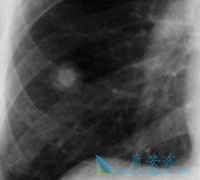

• 出现哪些肺癌症状表示患者肺癌转移了

出现哪些肺癌症状表示患者肺癌转移了

转移和复发是肺癌患者最致命的潜在威胁。转移复发后,治疗可能更加困难,患者的生活质量也随之下降,对于刚刚闯过一劫的病友们来说实属不易,刚刚平静下来,迎头再遭一击,于身于心都是一场莫大的煎熬。对于肺癌患者来说,出现哪些 肺 癌症状 要警惕复发 ...